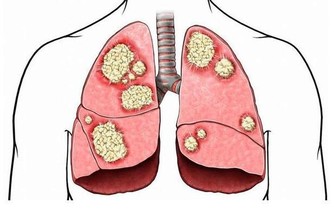

2、骨關節病

粗鹽熱敷4個部位治好4大頑疾可惜很少有人會用

與骨關節相關的風、寒、濕、痺、痛、關節僵硬等症,如頸椎病、肩周炎、風寒引起的風濕炎症和疼痛。

將粗鹽熱敷包裹在疼痛、怕冷的關節部位,每次熱敷20-40分鐘,至粗鹽逐漸冷卻即可。

“對於重度患者來說,只能輔助治療,不能完全取代藥物、手術等,應儘早就醫,以免耽誤治療最佳時機。